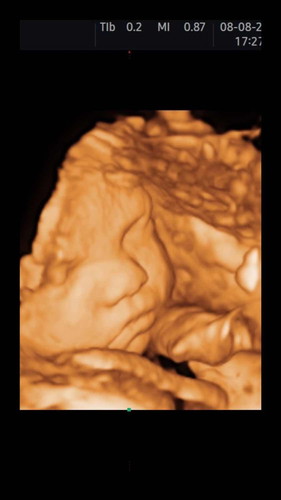

ทีมตุลา66 อายุครรภ์ 30 สัปดาห์ 2 วัน ซาวววด์4มิติได้แล้วววว ชัดมาก ไอ้ต้าวลูกครึ่งไทยโปรตุเกสของแม่ 🤍

ชัดมากค่ะแม่ บ้านนี้ก้ไปซาววันนี้30w1ไม่ชัดขนาดนี้ค่ะ